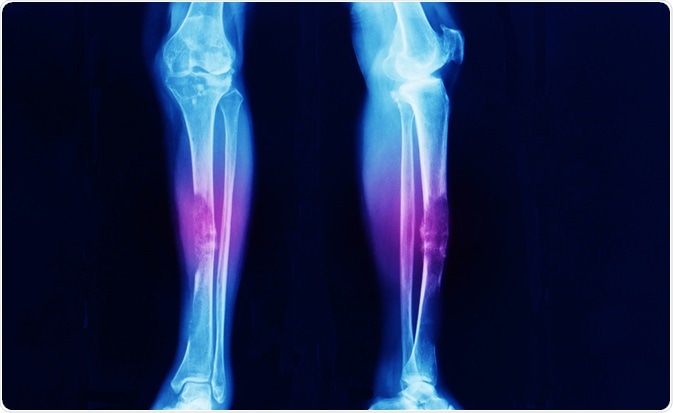

bone cancerImage Credit: Yok_onepiece / Shutterstock.com